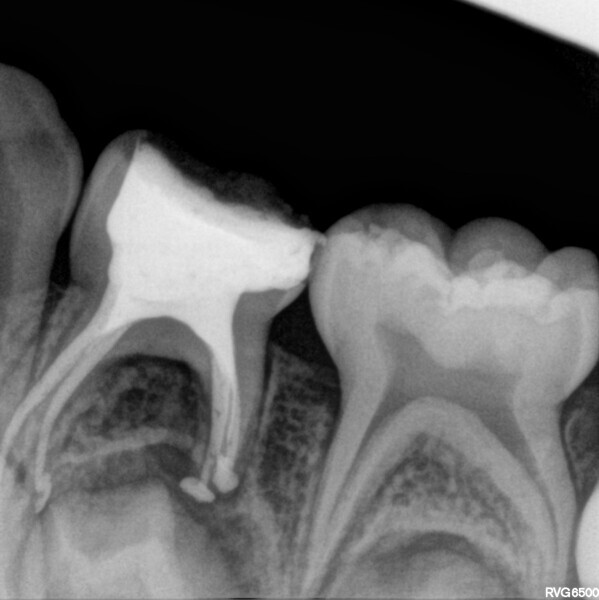

Cas 1 (Figs 1-4)

Cette patiente âgée de 4 ans et 7 mois présentait une douleur qui affectait la seconde molaire temporaire inférieure droite depuis plusieurs jours. L’examen clinique a révélé un gonflement du versant vestibulaire de la gencive et un œdème facial, ainsi qu’une carie occlusale profonde.Un diagnostic de nécrose pulpaire et d’abcès apical symptomatique ayant été posé, un traitement a été prescrit à la patiente, afin de maîtriser l’infection aiguë, et un nouveau rendez-vous a été fixé après l’antibiothérapie. Lors du deuxième rendez-vous, elle ne présentait plus aucune douleur et l’abcès buccal s’était partiellement résorbé. Il a été décidé de procéder à une pulpectomie et à la restauration de la dent. Dans ce cas, la dent présentait une extrusion excessive de matériau d’obturation. Après 15 mois, la réévaluation a confirmé l’absence de signes cliniques ou radiologiques pathologiques, et une apposition osseuse était visible dans la zone de la furcation.